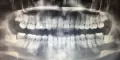

Мне 22 года, хочу поставить брекеты. В связи с этим есть 2 вопроса:

47 зуб необходимо будет установить после снятия системы.